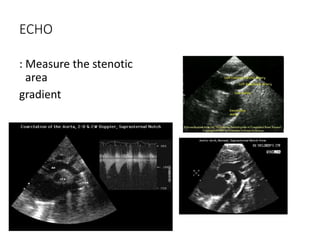

ECHO

: Measure the stenotic

area

gradient